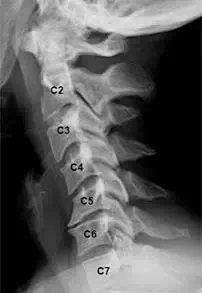

过去,颈椎病是40岁之后人的专利,但现在20~30岁的颈椎病患者到处都是,甚至还有得颈椎病的小学生!原因很简单:伏案久了,压力大了,自己又不懂得怎么调理,所以颈椎病提前光临了。

怎样才能知道自己的颈椎是否健康?日常生活中身体发出的小信号会提示不同类型的颈椎问题。

信号一:长时低头伏案工作,感觉到头晕难受,考虑为椎动脉型颈椎病;

信号二:不明原因的肩颈酸痛,手臂发麻,考虑为神经根型颈椎病;

信号三:正常直行走路却常出现“跑偏”问题,考虑为脊髓型颈椎病;

信号四:经常有不明原因的头晕、眼花、耳鸣、手麻、心动过速、心前区疼痛等一系列症状,考虑为交感神经型颈椎病。

如果同时出现上述几类症状,则考虑为混合型颈椎病。